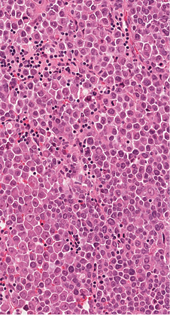

4 pav. Tik imunohistocheminiais metodais (MUC2) identifikuojama abortyvi mucinų produkcija pavienėse naviko ląstelėse

Imunohistocheminio profiliavimo metu nustatyta stipri difuzinė PanCK reakcija visuose komponentuose (3 pav.) ir menka, tačiau definityvi MUC2 žarninio tipo mucinų produkcija (4 pav.) kartu su tipiška KRAS geno 12-o kodono mutacija 2-ame egzone leistų klasifikuoti naviką kaip aukšto laipsnio (blogai diferencijuotą) adenokarcinomą. Ieškant biologinio pagrindo neįprastai naviko morfologijai paaiškinti atliktos papildomos imunohistocheminės reakcijos: Hep-Par1 (neigiama), INI1 (praradimo nėra), BRAF (neigiamas, tikėtina, nemutuotas), PMS2 ir MSH6 (reakcija išlikusi, nėra mikrosatelitų nestabilumo audinyje požymių), visose naviko ląstelių populiacijose patvirtintas jau biopsijoje identifikuotas difuzinis neuroendokrininis fenotipas (100 % Synaptophysin ir 95 % Chromogranin A ekspresija (5 pav.)). Ki67 proliferacinis aktyvumas buvo heterogeniškas ir rabdoidinės išvaizdos komponente siekė 90 proc., o likusiuose buvo perpus žemesnis (6 pav.).